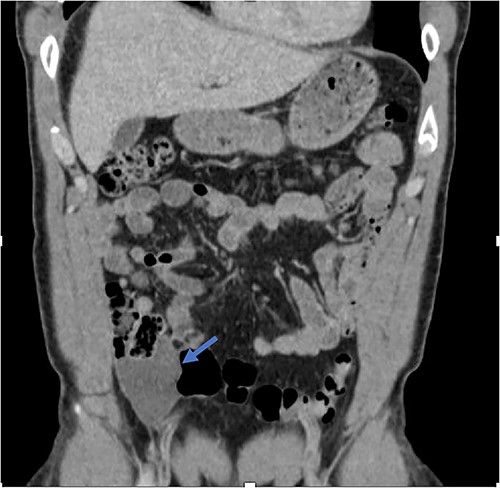

Low-grade appendiceal mucinous neoplasm (LAMN) is a rare entity present in ~1% of appendectomies [1, 2]. It is described by the World Health Organization (WHO) as one of three main categories of mucinous neoplasms: mucinous adenoma, LAMN, and appendiceal adenocarcinoma. The features of LAMN include acellular or cellular extra-appendiceal mucin, and there is a predisposition for female patients over 50 years of age [2–4]. If left untreated, sequelae include rupture of the appendix and mucocele with potential progression to pseudomyxoma peritonei. This is associated with high morbidity and mortality [1–4]. The clinical presentation of LAMN can be quite variable. Some patients are asymptomatic with the lesion incidentally identified during imaging or other operative procedures, while other patients may present with abdominal pain, weight loss, and acute appendicitis. In advanced disease, there may be the presence of pseudomyxoma peritonei, abdominal distension, and abdominal hernia [5–7]. Thus, imaging is an important tool in diagnosis and management. Computerized tomography (CT) is particularly useful when identifying legions in the ileocecal region, as it offers multi-planar, high-definition anatomic evaluation of the intra-abdominal contents [8]. LAMN, if ruptured, may appear on CT as fluid collections with a similar density to water in the absence of visualization of the appendix as a separate structure or evidence of active inflammation (Fig. 1). In this report, we describe a case of LAMN initially presumed to be appendicitis without the classic of an acute inflammatory process ultimately treated with surgical resection. We also review the available literature regarding the presentation, diagnosis, and management of LAMN.

Fluid collection is present in the expected location of the appendix that measures 5.2 × 2.9 × 6.6 cm (blue arrow). The appendix is not seen as a separate and distinct structure.